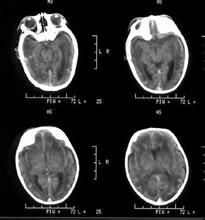

內容介紹 作者介紹 作品目錄缺血缺氧性腦病(HIE)是各種原因引起的腦組織缺血缺氧導致的腦部病變,最常見的是新生兒缺血缺氧性腦病,但也可發生在其他年齡段。新生兒缺血缺氧性腦病是圍生...

疾病介紹 疾病病因 發病機制 臨床表現 疾病治療新生兒缺氧缺血性腦病(hypoxie-ischemic encephalopathy HIE)是指在圍產期窒息而導致腦的缺氧缺血性損害。臨床出現一系列腦...

病因病理 臨床表現 診斷 輔助檢查 鑑別診斷外傷性癲癇(traumatic epilepsy)指繼發於顱腦損傷後的局限性或全身性痙攣,可分為早期癲癇(傷後1周內)和晚期癲癇(傷後1周到數年);其中...